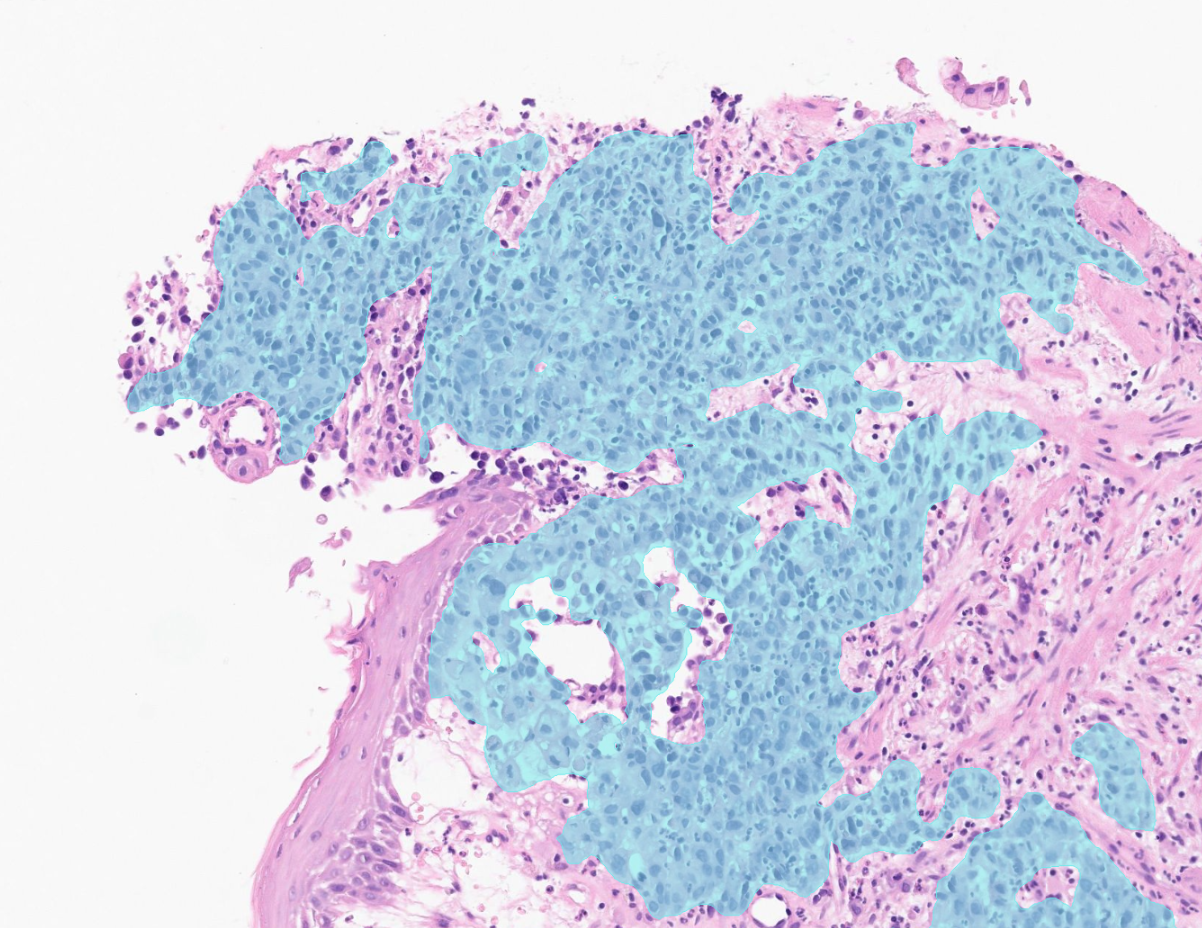

Manual screening for gastric carcinoma and Helicobacter pylori (H. pylori) is time-consuming and challenging. Subtle tumor foci and low bacterial density are subject to interobserver variability and workload pressure.

Aiforia® Gastric Suite uses AI to analyze digitized whole slide images to address these challenges. By highlighting suspicious areas directly on the slide, it enables efficient review while ensuring the pathologist remains in full control of interpretation and reporting.